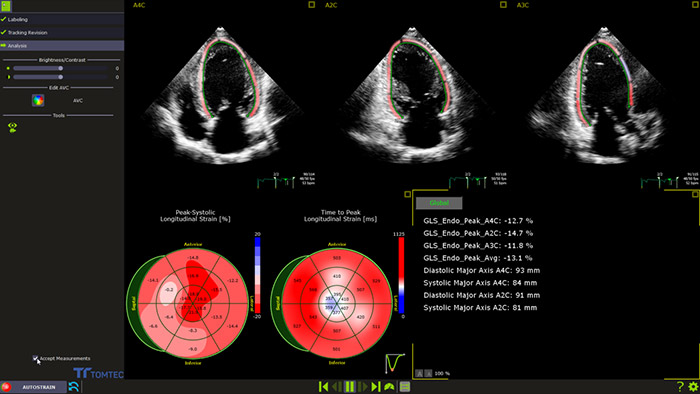

AutoSTRAIN

TOMTEC AutoSTRAIN bietet eine einfache Lösung zur Strain-Messung mit einem einzigen Knopfdruck und mittels Auto View Recognition und Auto Contour Placement mit einer Lernkurve von mehr als 6000 Bildern, um die Zuverlässigkeit zu stützen. AutoSTRAIN ermöglicht schnelle und reproduzierbare Messungen des linksventrikulären, globalen longitudinalen Strains (GLS) für die tägliche klinische Anwendung.